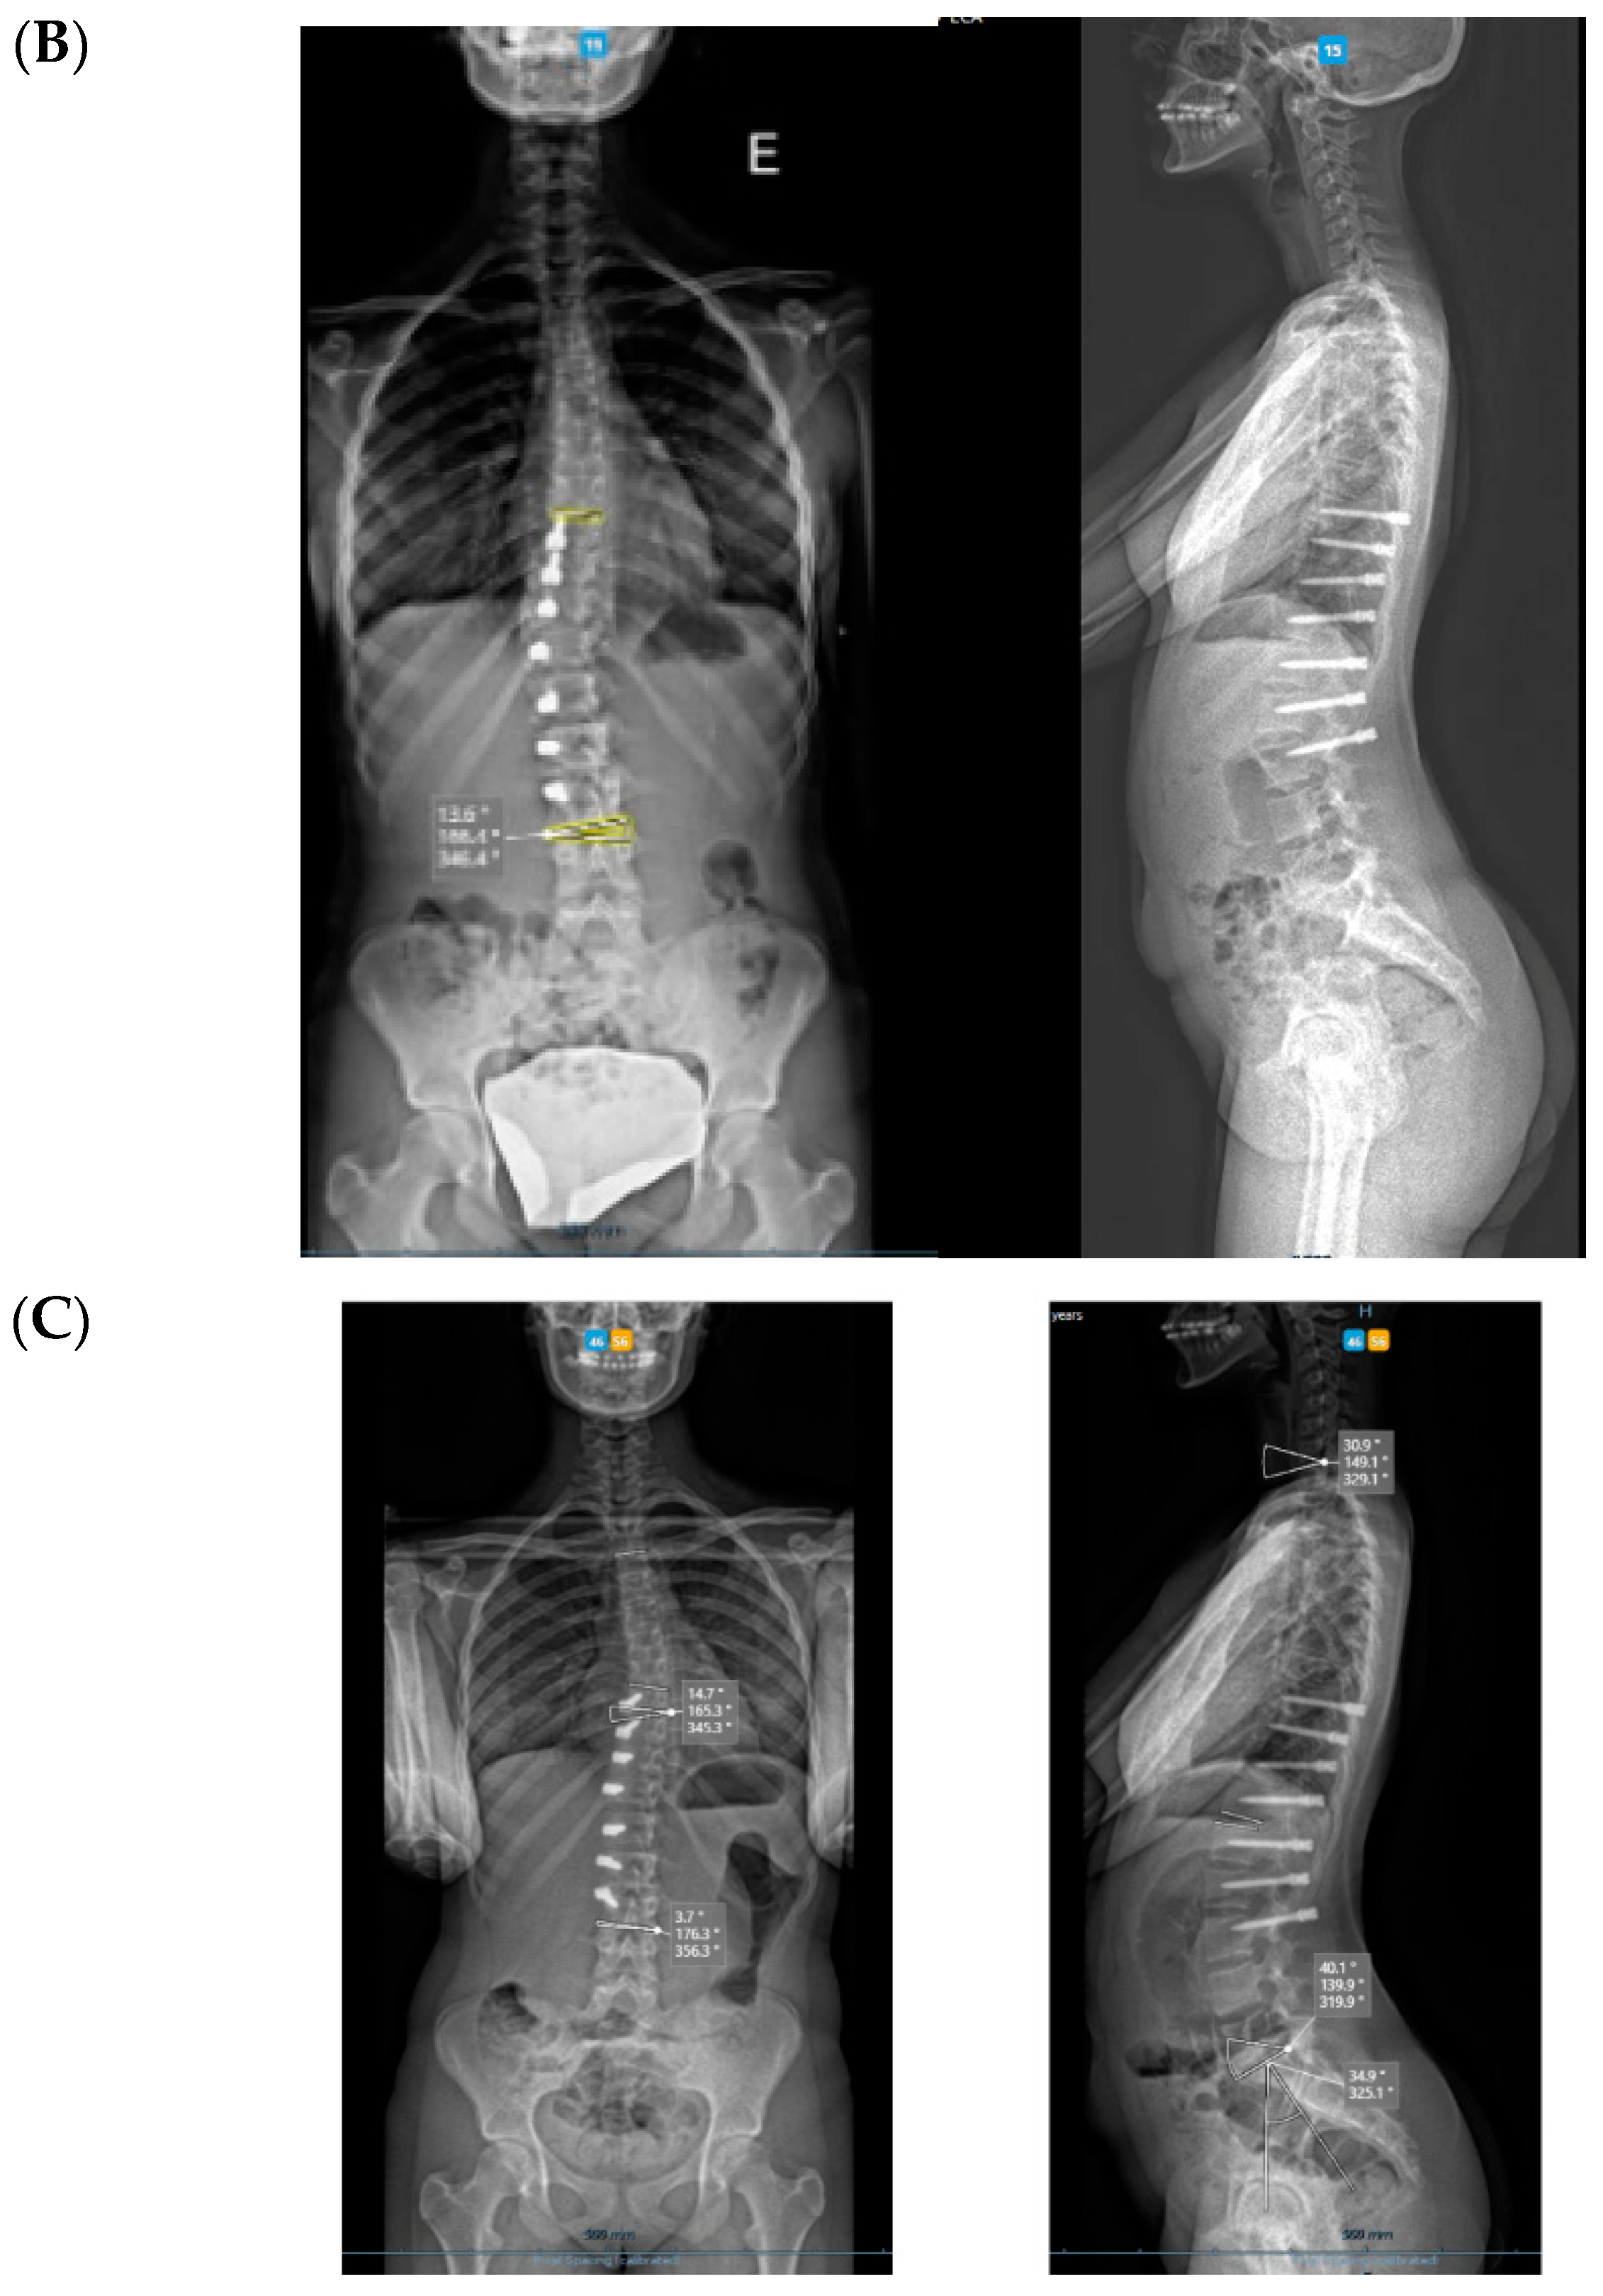

3. Results

All cases have progressed well with improvement of the curvatures with growth (Table 1) both in the coronal and sagittal alignment. At the 6-month FU, there was a mean 67.5% (34.8°) improvement in the main Cobb angle, but at 1 y, the oldest case over-corrected, and this was clinically noted by the girl, who pointed out that her flank symmetry had recently inverted (from one side to the other) after being symmetrical for some time (Figure 6).

Regarding the sagittal profile, we have looked at three different segments—T1–T9, T10–L3, and L3S1. In this 6-month period, the proximal segment in these three cases had increased kyphosis by 7.7°; the intermediate segment had increased lordosis by 10.9°; and the distal lumbar segment had decreased lordosis by 13.6°. However, in the only case that underwent tether release due to coronal over-correction, it is interesting that the thoracic kyphosis increased, the intermediate lordosis decreased, and the distal lumbar lordosis increased post-operatively; as such, spinal sagittal balance was well-maintained.

Concerning de-rotation, we can assess the apical vertebral rotation on the pre-operative radiograph as a Cobb grade +3 (Nash–Moe 50%) that improved to a Cobb grade +1 (Nash–Moe of 0%) in the last FU film (Figure 7) one year later.

Spinal growth is difficult to assess accurately in a coronal deformity that is gradually improving by the surgical procedure in a spine that is still growing, as the two chosen spots will gradually distance away from each other through these two mechanisms. We have taken the same midpoint in the distal endplate of the instrumented vertebra or on the proximal endplate, which is always on the same proximal junctional vertebra (Figure 8). Over this period of 6 months, the referred distance has increased by a mean of 7 mm (min. 3–max. 16 mm) in the three cases, and the oldest girl (56.7° Cobb angle pre-op) saw the greatest increase. In the case of such flexible scoliosis with a more severe Cobb angle that corrected significantly with this technique (Figure 8 and Figure 9), it is obvious that the two chosen spots will distance more from each other than in scoliosis with a smaller Cobb angle. This increase in spinal length between the two endplate spots is not spinal growth per se, but differentiating these two mechanisms is difficult.

3.1. Complications

The only case with a 15-month follow up progressed to coronal over-correction and had to be revised (under local anaesthetic) for tether release at four levels (Figure 9A,B). Since then, she has been doing well clinically and radiologically. This complication may have happened because correction obtained at the index procedure was too much, with a Cobb angle of 13.6° in the immediate post-operative erect radiograph (pre-op Cobb angle 56.7°) in a girl rated Sanders 3 (Figure 9C).